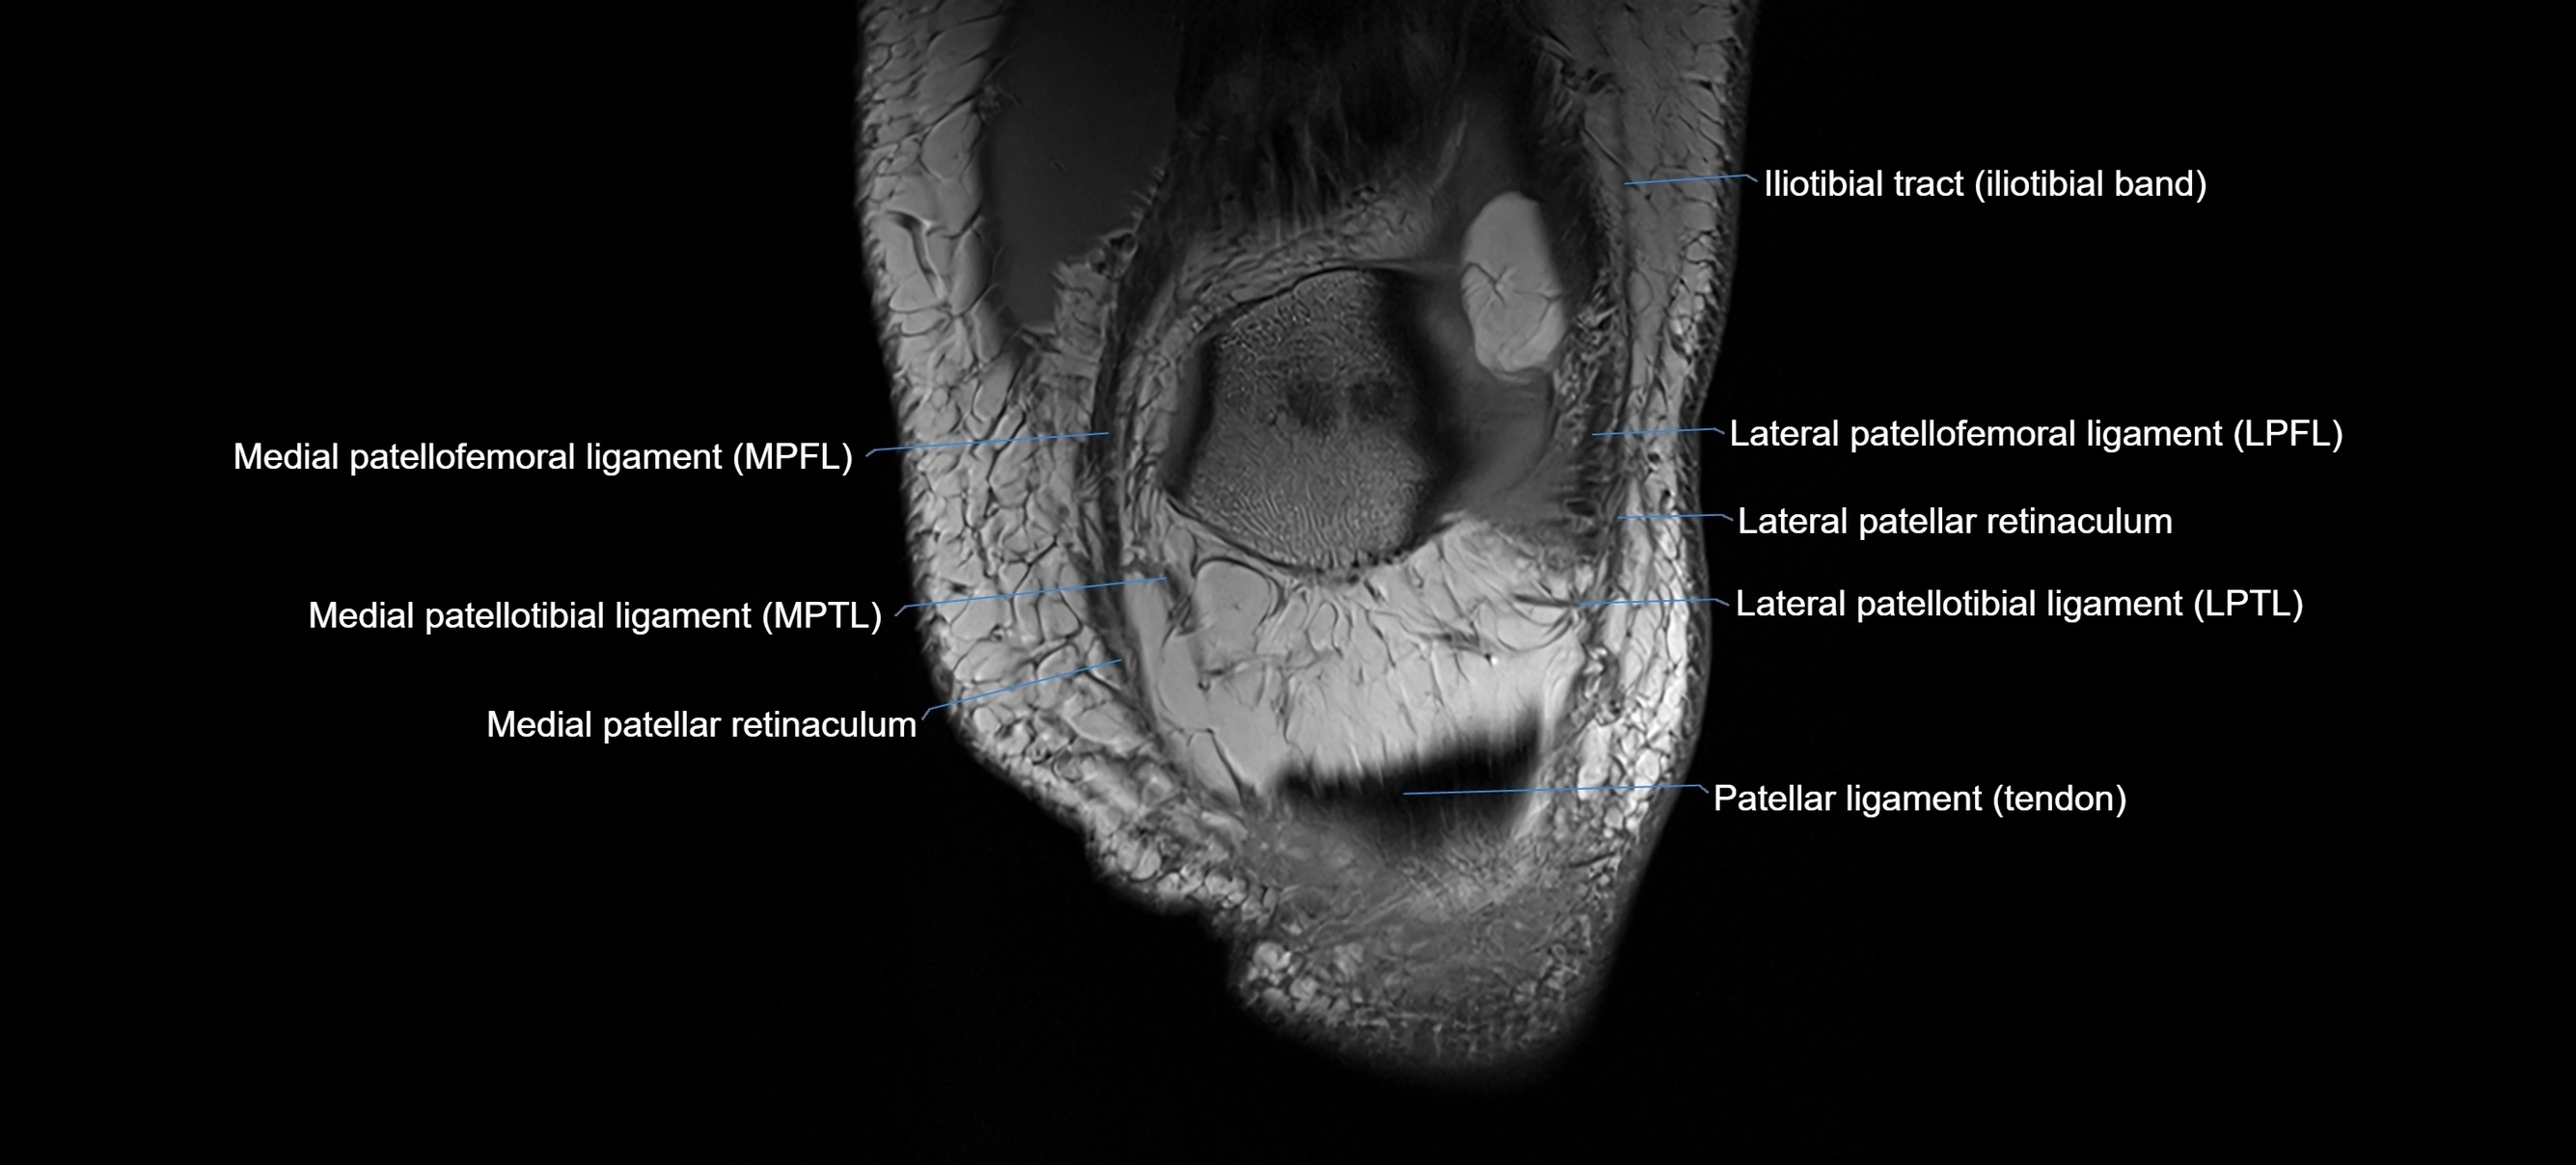

MRI images

image